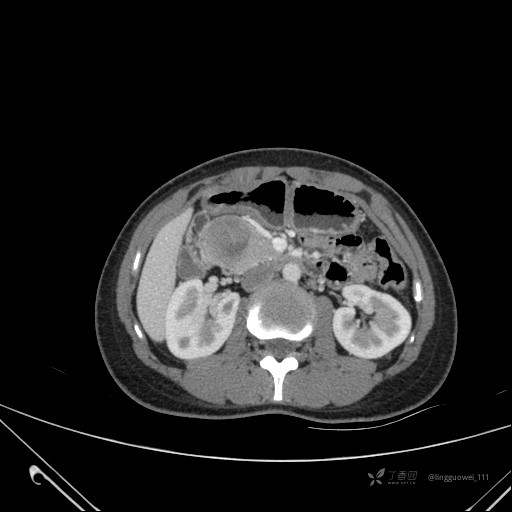

患者性别:女

患者年龄:28岁

主诉:体检发现胰腺病变,行 CT检查。

动脉期:

img